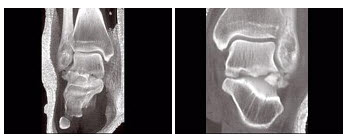

141、单项选择题

男,56岁,踝关节肿胀,有糖尿病史,结合图像,最可能的诊断是()